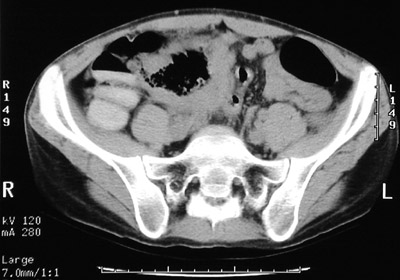

There is a mass with a central lumen in this abdominal CT scan. This proved to be a large B cell lymphoma involving the sigmoid colon in a patient with AIDS.